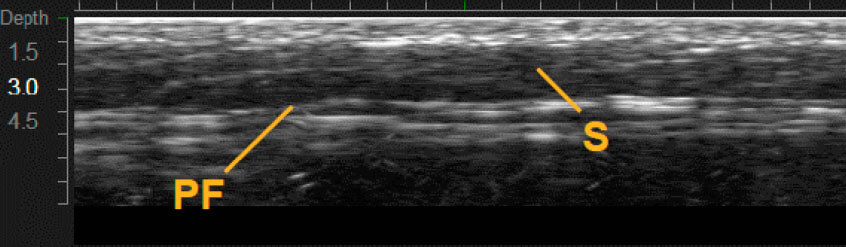

Приклади варіантів структури шкіри між індивідуальними пацієнтами 1,12

Візуалізація в реальному часі є основою Ultherapy®

MFU-V дає змогу лікарям точно бачити і враховувати всі анатомічні особливості в індивідуальному плані лікування, який буде ефективним.1